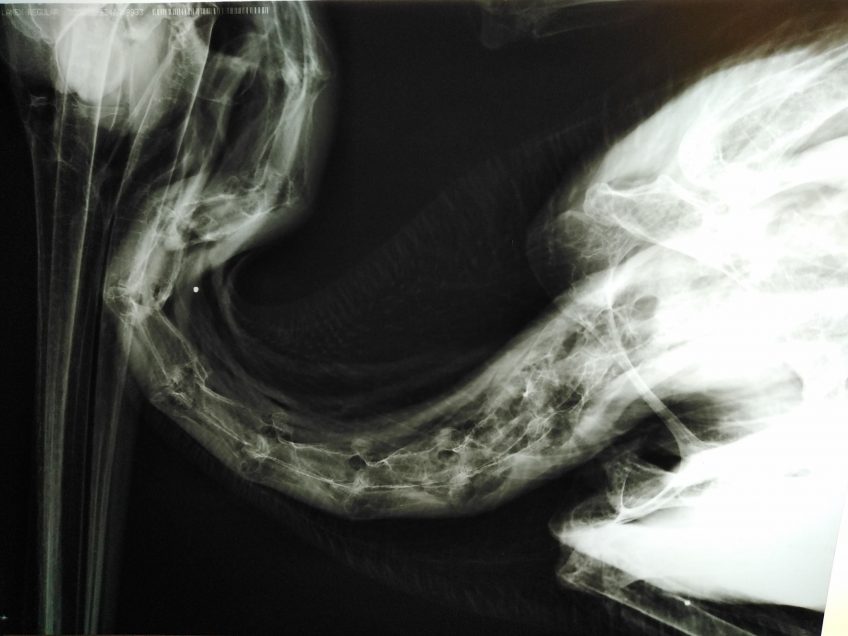

Σύμφωνα με πληροφορίες ο αργυροπελεκάνος βρέθηκε σε άθλια κατάσταση, πυροβολημένος, αφού βρέθηκαν σκάγια στην περιοχή του τράχηλου και της φτερούγας. Η ύπαρξη σκαγιών επιβεβαιώθηκε και από τις ακτινογραφίες που ελήφθησαν στο ιατρείο του κου Καλτσά.